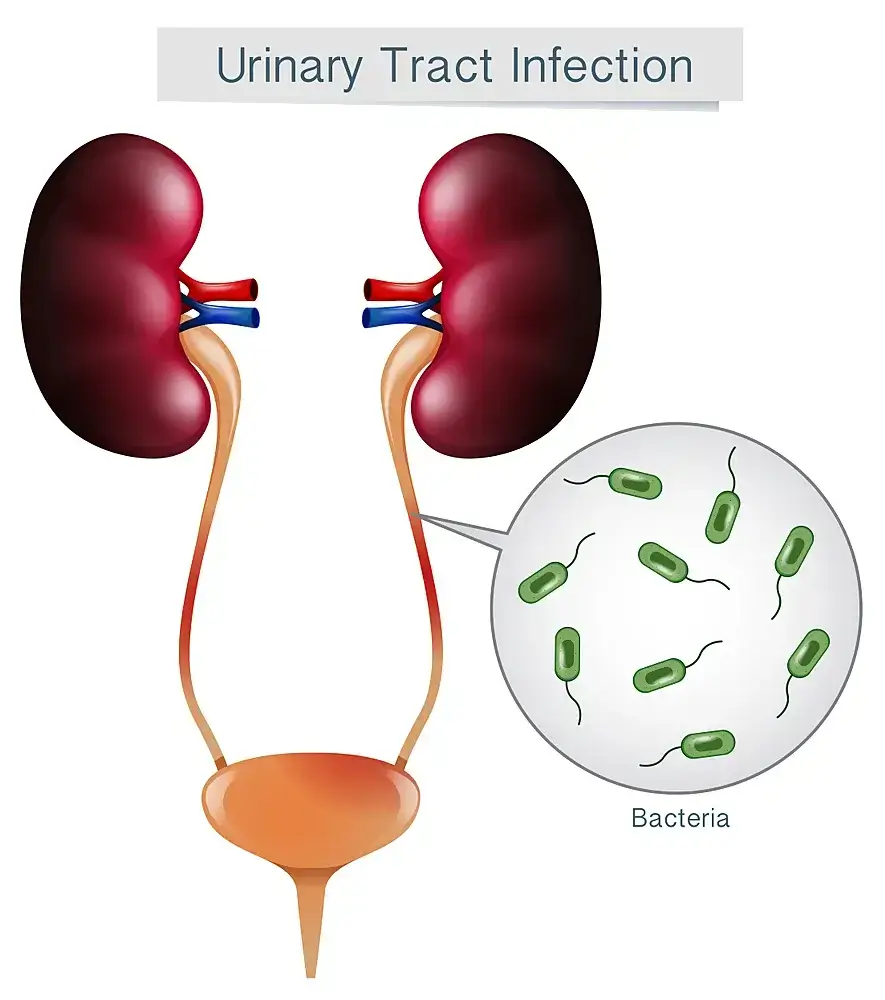

Urinary Tract Infections (UTI)

Urinary tract infections (UTIs) are the most common type of infection in women. They occur when bacteria from the environment or your own body get into your urinary tract, which can happen when you have intercourse, drink water from a contaminated source, or use the bathroom while you have a UTI. The symptoms of a UTI can vary depending on the location of the infection.

Urinary tract infections (UTIs) are a common infection in women and can be caused by a variety of organisms, both bacterial and fungal. Symptoms can include frequent urination, urgency to urinate, burning on urination, and a feeling of fullness after urinating.